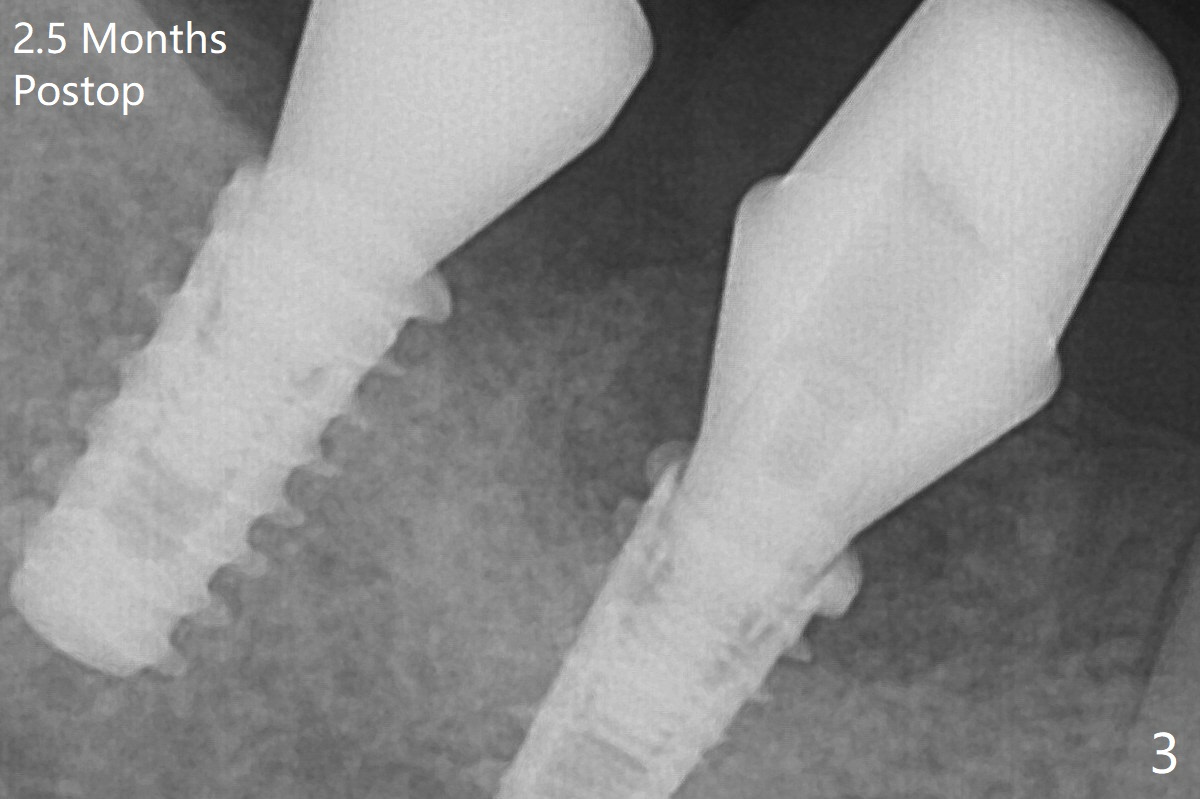

Note bone growth, especially at #30, 2.5 and 4 months postop (Fig.3,4). In fact the abutments are incompletely seated. The crown of #30 is loose with foul smell 2 years 8 months post cementation. It is painful to reinsert the crown/abutment after proximal reduction. A healing abutment is placed (Fig.5). When the incompletely seated abutment at #31 is removed, there is also smell. After separation from the crown, the abutment of #31 returns to the site with change in insertion position, while a smaller abutment has to be used at #30 (Fig.6) due to use of the small healing abutment earlier (Fig.5). A good piece of news is the presence of the bone between the implants (Fig.5,6 *), which contributes to interimplant papilla.